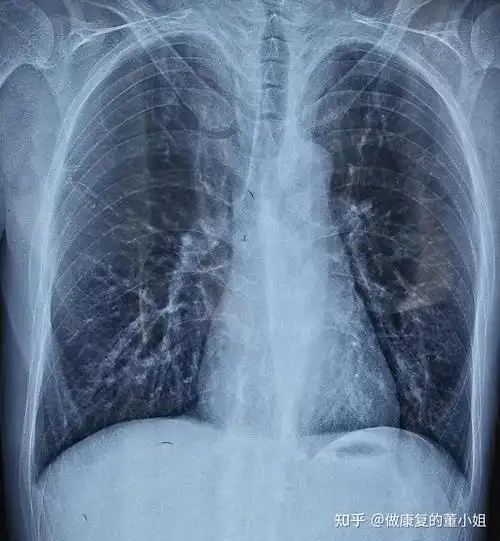

康复案例22——强直性脊柱炎如何功能锻炼